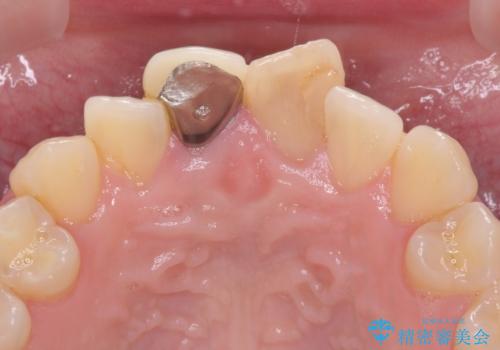

レントゲン写真より、変色してしまった歯は根管治療がされていなかったため、根管治療後にファイバーコアによる土台築製を行い、前歯2本をオールセラミッククラウンにて補綴することとしました。

変色とともに、捻れていたことも気になっていたので、その両方を解決させることとしました。